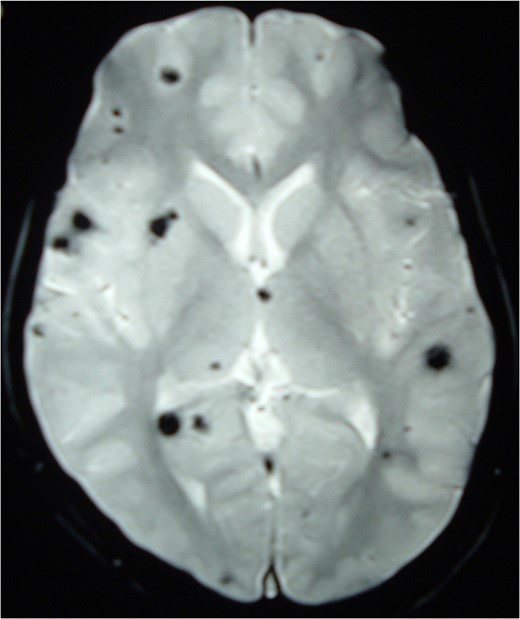

Magnetic resonance imaging (MRI) of the brain and spine showed multiple hypointense lesions in the brain and one mixed intense lesion with a hyperintense rim intrinsic to the spinal cord at the level of C5 with evidence of fresh bleeding (Figs 1–3). He was diagnosed with multiple cerebral cavernomas and an acutely bleeding spinal cavernoma. The patient was scheduled for a laminectomy and total excision of the spinal cavernoma and to control further hemorrhage. Bone removal was limited to the site of malformation. The lesion was identified by the bluish discoloration on the dorsal surface of the spinal cord (Fig. 4). A myelotomy was made over the discoloration and the lesion was excised inside out. Intraoperative evoked potential monitoring was not used for our procedure due to lack of availability.

Intraoperative image at C5 showing subpial bluish discoloration at the spinal cord surface with underlying cavernous angioma.

Complete resection of the intramedullary lesion remains the general consensus to treat pediatric intramedullary cavernomas based on previous case reports [1, 4, 5, 9]. The lesion appears as a bluish discoloration on the dorsal surface of the spinal cord. Intraoperative ultrasound is used to localize the lesion and a myelotomy is done over the discolored region to completely resect the lesion [4, 9]. The gliotic plane surrounding the lesion is used as a demarcation to remove the lesion. Intraoperative electrophysiological monitoring with somatosensory evoked potentials and motor-evoked potentials may be used to monitor and prevent any impending perioperative neurological deficits [1, 9]. Histology of the resected lesion usually confirms the appearance of dilated thin-walled vascular structures lined by a single layer of endothelium without any intervening neural tissue [2, 9]. Postoperative MRI to confirm complete resection is desired [2].